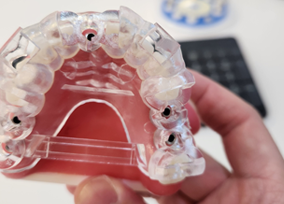

컴퓨터 분석 임플란트

3D 모의수술을 통한 정확성 UP!

3D CT, 구강 스캐너 등 디지털 정밀 진단을 접목한 모의 수술로 사전에 잇몸뼈, 신경, 보철 등을

모두 고려하여 식립 위치를 결정하여 개개인에게 맞는 수술 유도 장치를 제작하는 방법입니다.DIGITAL IMPLANT

컴퓨터 분석 임플란트 수술을 위한 가이드를 원장이 직접 디자인하고 제작합니다.

원장이 직접 디자인하고 제작하는 가이드를 활용하여 정교한 식립